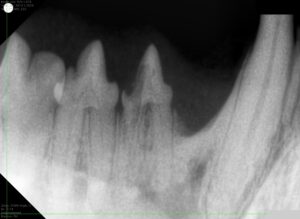

麻酔をかけた状態で、歯科レントゲン撮影を行い表からは見えない歯の根や歯の内部に異常がないかまで確認します。また、歯を1本ずつ触り歯周病によって歯周ポケットができていないか、出血がないかなども確認します。

歯科レントゲンにより、溶けている歯は1本だけであり歯根と顎の骨の癒着も少ないことがわかりました。

問題を起こしている歯を抜歯し、他の歯は徹底的に歯周病の原因となる汚れを除去(スケーリング)して終了です。